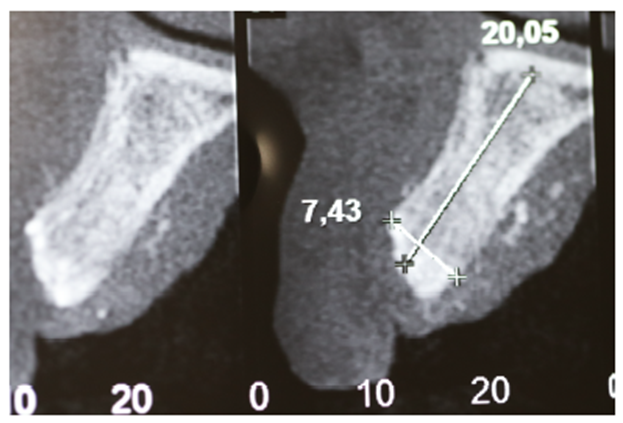

Foi solicitada a tomografia computadorizada total de maxila, com medidas de altura e espessura para planejamento cirúrgico.

Observou-se extenso defeito ósseo nos sentidos horizontais e verticais em pré-maxila (Figuras 2 e 3), sendo necessária a realização de uma extensa regeneração óssea guiada, com enxerto ósseo particulado (Geistlich – Bio-Oss), membrana de PTFE-d com reforço de titânio e membranas de fibrina autógena (LPRF).

Cinco meses após a remoção da membrana, foi realizada nova tomografia computadorizada com medidas de altura e espessura para planejamento dos implantes dentários, mostrando o sucesso obtido através da técnica de enxertia óssea com a membrana de PTFE-d (Figuras 14 e 15).